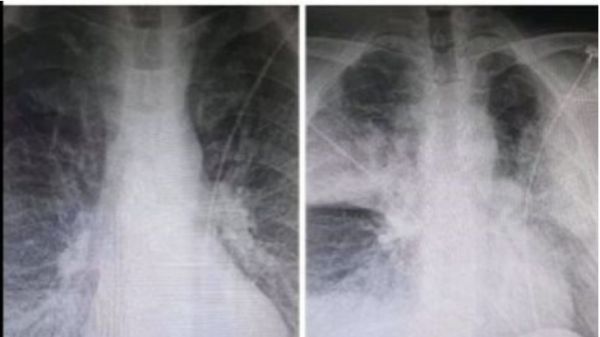

Είναι η όχι αυτοί οι πνεύμονες ασθενούς με κοροναϊό; – Σάλος στο διαδίκτυο, τι ισχύει τελικά

Αλαλούμ έχει προκαλέσει η φωτογραφία με τις δύο ακτινογραφίες που ανήρτησε στο Facebook ακτινολόγος από το ΚΑΤ και που σε αυτήν αποτυπώνεται η ραγδαία επιδείνωση που προκαλεί ο κοροναϊός στους ασθενείς.